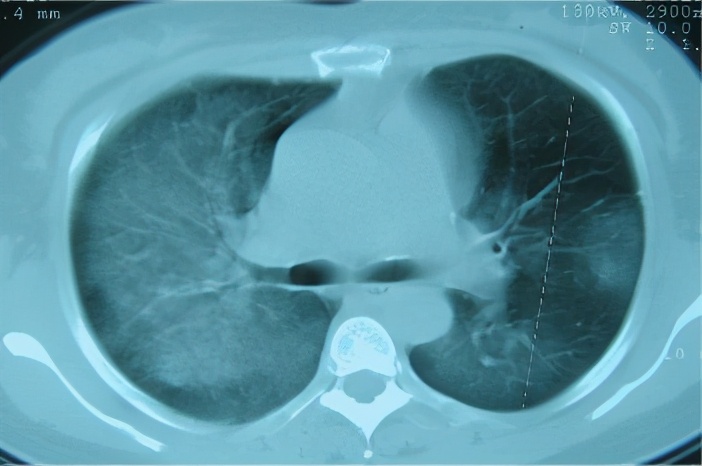

后来,患者到中日医院就诊,这是2015-9-30在中日医院的胸部CT(右)与2015-8-20胸部CT(左)有进一步吸收的对比:

急性和亚急性过敏性肺炎的胸部CT的差距就比较明显,我们可以看到典型改变:小叶中心结节,边界不清,弥漫分布;轻症患者CT也可无明显异常;磨玻璃样/实变,片状或弥散,支气管血管束,下叶分布;肺气肿或马赛克征象。

胸部CT:不规则索条影、网格、结节(小叶中心)、磨玻璃;肺结构改变更明显,支气管扩张,蜂窝肺;肺皱缩(上叶)下叶代偿性肺气肿,但是无钙化和空洞;马赛克(主要见于亚急性/慢性);支气管血管束增重。

2)CT特点: 马赛克/气体陷闭、磨玻璃、细小结节、蜂窝肺、纵膈淋巴结肿大等最常见。